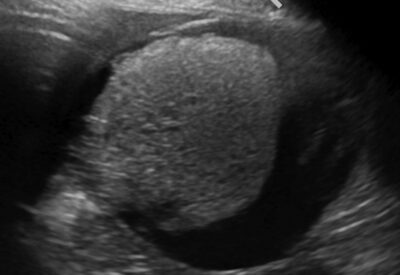

外科 腫瘍科(がん)外科 犬の前立腺癌 腫瘍科(がん)外科 猫の脾臓の肥満細胞腫 腫瘍科(がん)外科 犬の副腎腫瘍(副腎皮質腺癌) 腫瘍科(がん)外科 犬の扁桃の扁平上皮癌 外科 猫の尿道閉塞 外科 胆嚢粘液嚢腫 腫瘍科(がん)外科 犬の肝臓腫瘍(肝細胞癌) 腫瘍科(がん)外科 犬の低悪性度口腔内メラノーマ 整形外科(骨・関節の病気)外科 レッグペルテス(大腿骨頭壊死症) 消化器科外科 巨大結腸症(便秘) 腫瘍科(がん)外科 犬の骨盤腔内腫瘍 膣腫瘍 腫瘍科(がん)外科 犬の腎臓腫瘍 前のページ最新12345最初次のページ